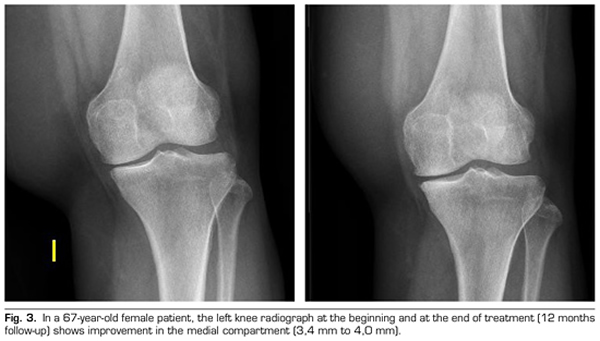

Regarding the radiological variables, when evaluating 53 out of the 115 patients who completed one year of follow-up after ozone treatment, it was observed that the internal compartment increased significantly by 4.12 ± 1.41 mm to 4.4 ± 1.35 mm (p = 0.0008) and the external compartment increased from 6 ± 1.37 to 6.16 ± 1.4 mm (p = 0.0753) (Table II). Two clinical cases are presented as a sample of the radiological change in the internal and external compartments (Figures 2 and 3).

After a year of follow-up with radiological controls on 53 out of the 115 patients in the study, ozone (O2-O3) has been able to increase the minimum joint space of the medial compartment (from 4.12 to 4.44 mm) and the lateral compartment (from 6.0 to 6.16 mm), reversing knee osteoarthritis in our case series. This finding suggests the disease modifying effect of ozone (O2-O3) on knee osteoarthritis, findings that is consistent with the recently reported by Fernández-Cuadros et al. (9).